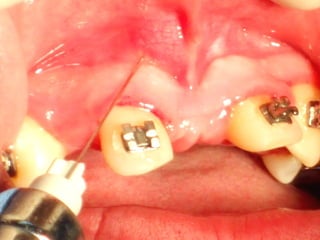

Mini-implantes para apoyo de fuerzas ortodóncicas

Mini-implantes para apoyode fuerzas ortodóncicas